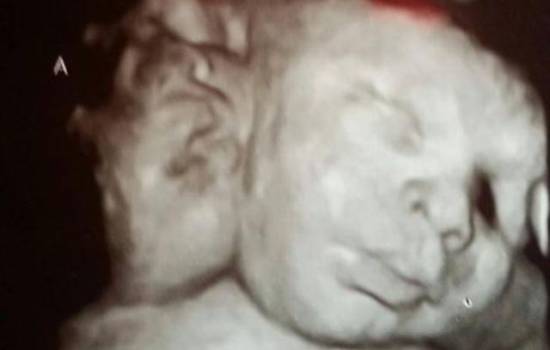

Таких детей – один на миллион, у ребенка две самостоятельно функционирующие головы, но одно тело и одно сердце, а родители очень рады пополнению семейства.

Аса и Эли Хамли родились у тридцатичетырехлетних родителей Робин и Мишель. На языке медицины их отклонение называется dicephalic parapagus, то есть состояние близнецов, когда все органы, за исключением голов, у них общие.

Аса и Эли имеют три легких, и, за исключением несерьезных нарушений в сердце, их организм находится в полном порядке.

Вследствие того, что почти все органы и кровеносная система у близнецов одни на двоих, их невозможно разделить, сохранив жизнь обоим.